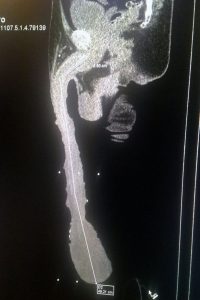

მსოფლიოში ყველაზე დიდი, 18,9 ინჩის (47სმ) სიგრძის პენისის მქონე მამაკაცმა, მექსიკელმა რობერტო კაბრერამ სასქესო ორგანოს შემცირებაზე უარი განაცხადა. „მე კმაყოფილი ვარ ჩემი პენისის ზომით. ვიცი, რომ ამ ზომის სასქესო ორგანო მსოფლიოში არავის აქვს. თავისუფლად შემიძლია გინესის რეკორდების წიგნში მოვხვდე, მაგრამ იქ მსგავს პრეცედენტს ადგილი არ ჰქონია”, – განაც

ექიმები ამბობენ, რომ პენისის შემცირების ოპერაციის გაკეთება კაბრერას იმისთვის ურჩიეს, რომ მას ნორმალური სქესობრივი ცხოვრება ჰქონდეს და ბავშვი ეყოლოს. თუმცა 54 წლის მამაკაცმა ეს შეთავაზებები უარყო და „განსაკუთრებულად“ დარჩენა არჩია. მექსიკის კანონმდებლობის მიხედვით, რობერტოს შშმ პირის სტატუსით სარგებლობის უფლება აქვს, ვინაიდან დიდი პენისი მას ყველა ფუნქციის ნორმალურად შესრულების საშუალებას არ აძლევს. თავად რობერტო ამ ფაქტს იუმორით უყურებს